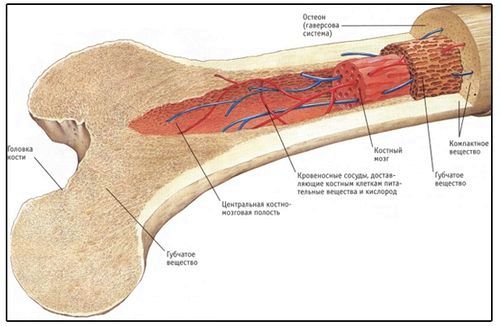

Будова кісткової тканини

У скелеті людини існує два типи кісток:

Кость у дорослої людини має пластинчасту будову з правильно розташованими колагеновими волокнами. Тонкий і дуже щільний шар кальцинованої тканини утворює зовнішню частину кістки. Корковий шар вистилає в диафизах мозкову порожнину, в якій міститься кістковий мозок.